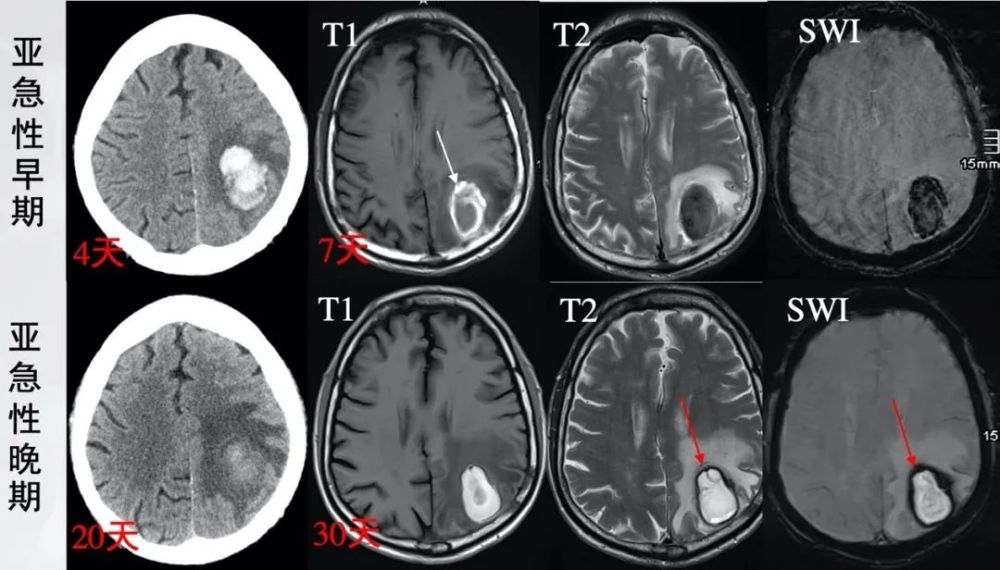

图5 65岁男性 , 表现为头痛、命名障碍、失用、轻度感觉性失语 。 (Radiopaedia , by Yves Leonard Voss)

亚急性早期(起病7天):T1像高信号环(白箭)代表血肿周边首先被氧化的高铁血红蛋白 , 中心的去氧血红蛋白仍呈低或等信号 , 外周的低信号代表血肿周围水肿带 。 T2像无论高铁血红蛋白和去氧血红蛋白均呈低信号 , 周围环绕高信号水肿带 。 SWI像示低信号 。

亚急性晚期(起病30天):细胞外高铁血红蛋白使血肿中心T1像、T2像、SWI像均呈高信号;T2像和SWI低信号环(红箭)代表血肿周边巨噬细胞和胶质细胞内的的含铁血黄素 。